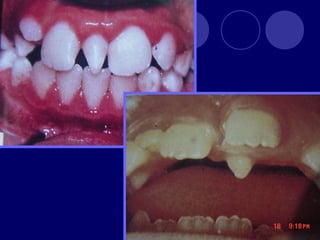

SUPERNUMERARIOS

 :aumento en el numero de dientes.

 Temporal: 0.5%

 Permanente: 3%

 Maxilar

 Masculino

 Únicos

 Múltiples: Sx.

Gardner, disostosis

cleidocraneal

 Rudimentarios:

Tuberculado

Cónico

 Complementarios

 Mesiodens

 Distomolar

 Paramolares

SUPERNUMERARIOS  :aumento enel numero de dientes.

• 11.

 Temporal: 0.5% Permanente: 3%  Maxilar  Masculino  Únicos  Múltiples: Sx. Gardner, disostosis cleidocraneal